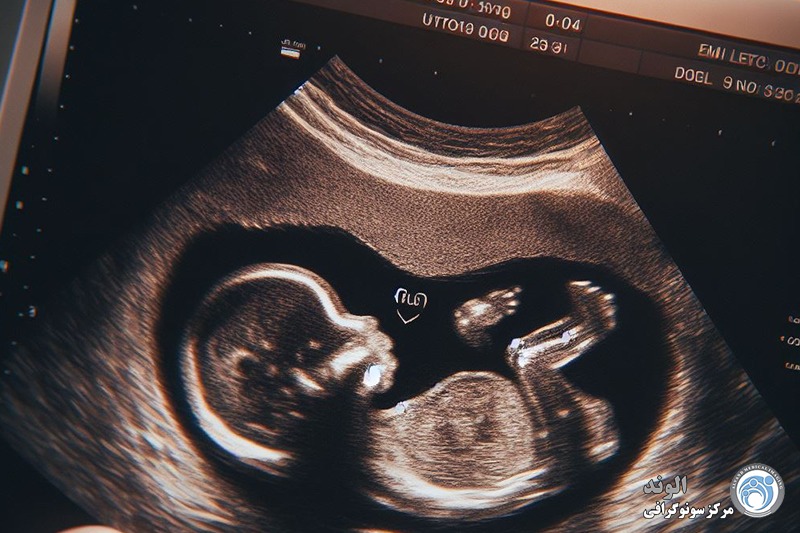

تعداد جنین ها و در نتیجه اینکه آیا ما دوقلو خواهیم داشت یا چرا که نه، سه قلو! همچنین به طور دقیق تاریخ لقاح کودک را تعیین می کند، که برای نظارت بر رشد آن و عدم خطر فراتر از دوره بارداری ضروری است.

نشاط نوزاد: سونوگرافیک فعالیت جنین را در صورت متحرک بودن و زیاد بودن حرکات مشاهده می کند.

مورفولوژی نوزاد: پزشک مطمئن می شود که هیچ گونه ناهنجاری مورفولوژیکی وجود ندارد. جمجمهاش را معاینه میکند، بررسی میکند که دو دست و دو پا دارد و هر یک از اندامهایش بهخوبی به ۳ قسمت (ساعد، بازو، دست) تقسیم شدهاند که قلبش در سمت چپ است. همچنین توجه می کند که دیواره قدامی شکم به خوبی بسته باشد، معده و مثانه در جای خود قرار گیرند. او نگاه می کند تا ببیند آیا ستون مهره (ستون فقرات) هیچ گونه ناهنجاری را نشان نمی دهد... توجه ویژه ای نیز به محیطی که نوزاد در آن زندگی می کند معطوف می شود: میزان مایع آمنیوتیک، مطالعه و محل جفت.